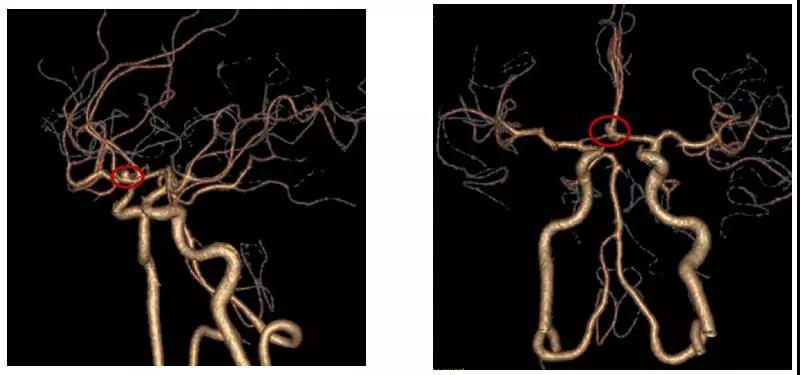

經(jīng)過充分的術(shù)前準備,李雪松醫(yī)療團隊僅用了兩個多小時就順利完成手術(shù)。術(shù)后當天,患者就睜開了雙眼,肢體、語言功能等方面都正常,家屬臉上露出了滿意的笑容。目前,患者正在積極的康復中,不久就能出院。

患者術(shù)后頭部CTA

術(shù)后頭部CT骨窗